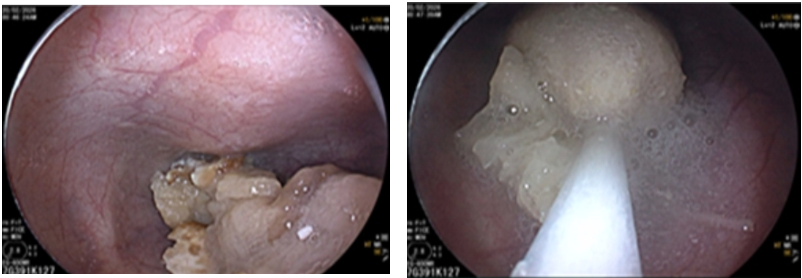

Nội soi dạ dày cho thấy thức ăn mắc lại trong thực quản. Dị vật được lấy ra kịp thời.

Ở người cao tuổi, phản xạ nuốt giảm, răng yếu, khả năng nhai kém. Những thực phẩm dai và nhiều xơ như măng, thịt bò, thịt gà rất dễ gây nghẹn nếu không được cắt nhỏ và nhai kỹ.